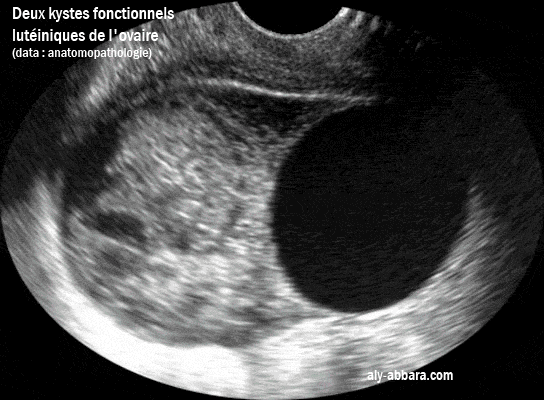

Deux kystes lutéiniques de l'ovaire gauche dont un avec une hémorragie intra-kystique

(Données de l'examen anatomopathologique)